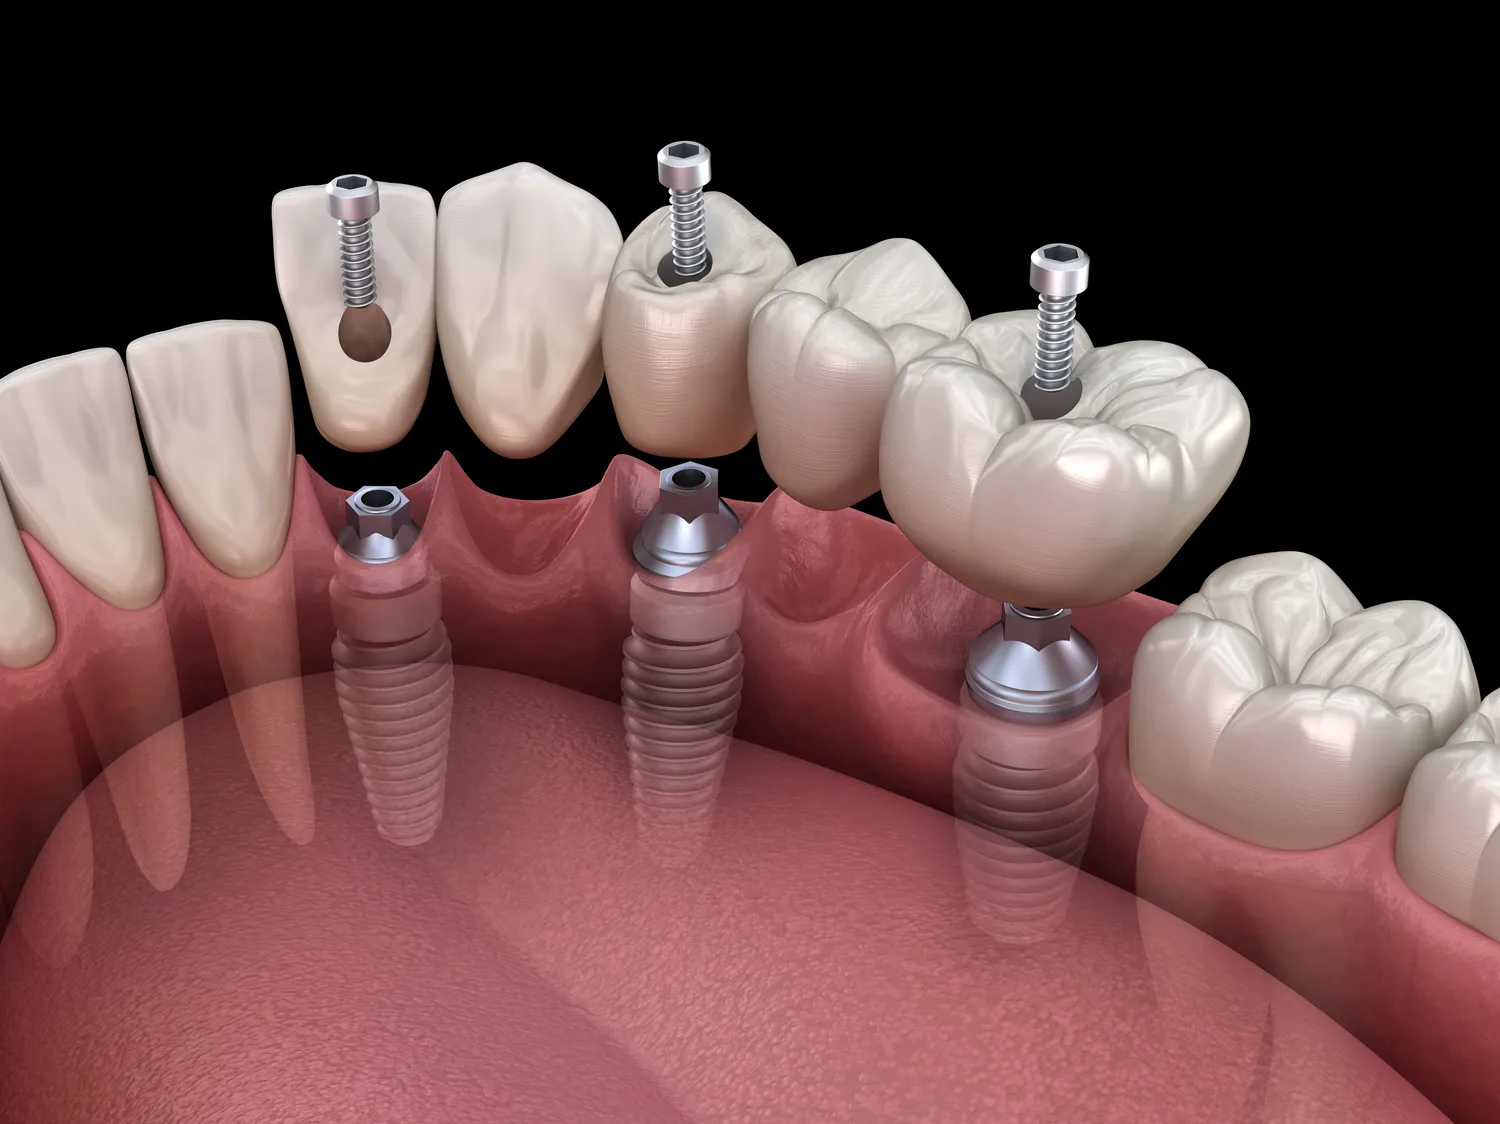

Implanty zębów to rozwiązanie, które zyskuje na popularności wśród osób borykających się z utratą zębów. W przeciwieństwie do tradycyjnych protez, które mogą być niewygodne i wymagać częstej wymiany, implanty oferują trwałe i stabilne wsparcie dla sztucznych zębów. Proces ich zakupu zaczyna się od konsultacji stomatologicznej, podczas której lekarz ocenia stan zdrowia pacjenta oraz wykonuje niezbędne badania obrazowe. Następnie następuje wszczepienie implantu, który jest wykonany z biokompatybilnych materiałów, co pozwala na integrację z kością szczęki. Po kilku miesiącach, gdy implant się zagoi, można przystąpić do umocowania korony, co daje efekt bardzo zbliżony do naturalnego uzębienia. Dzięki temu osoby noszące implanty mogą cieszyć się pełną funkcjonalnością jamy ustnej, w tym możliwością jedzenia twardych pokarmów oraz swobodnym mówieniem.

Na rynku dostępnych jest kilka rodzajów implantów zębowych, co pozwala na dostosowanie leczenia do indywidualnych potrzeb pacjenta. Najpopularniejsze są implanty endoossealne, które wszczepia się bezpośrednio w kość szczęki. Charakteryzują się one dużą stabilnością i trwałością, a ich kształt oraz rozmiar mogą być dostosowane do konkretnego przypadku. Innym rodzajem są implanty subperiostealne, które umieszcza się pod błoną śluzową, ale na kości. Stosuje się je głównie u pacjentów z niewystarczającą ilością kości do wszczepienia tradycyjnych implantów endoossealnych. Warto również wspomnieć o implantach mini, które są mniejsze i często stosowane w przypadkach, gdzie nie ma miejsca na standardowe implanty. Każdy z tych typów ma swoje zalety i wady, dlatego kluczowe jest skonsultowanie się z lekarzem, który pomoże wybrać najlepszą opcję w zależności od stanu zdrowia pacjenta oraz jego oczekiwań.

Proces leczenia implantami zębowymi może trwać od kilku miesięcy do nawet roku, w zależności od indywidualnych okoliczności pacjenta oraz wybranej metody leczenia. Po pierwszej konsultacji i wykonaniu badań diagnostycznych następuje etap wszczepienia implantu. W przypadku zdrowej kości proces gojenia trwa zazwyczaj od trzech do sześciu miesięcy, podczas których implant integruje się z kością szczęki. W sytuacjach, gdy konieczne są dodatkowe zabiegi, takie jak przeszczepy kości czy podniesienie dna zatoki, czas ten może się wydłużyć. Po zakończeniu procesu gojenia następuje kolejny krok – umocowanie korony na implancie. Cały proces wymaga cierpliwości i regularnych wizyt kontrolnych u stomatologa, który monitoruje postęp gojenia oraz ocenia stan implantu. Warto pamiętać, że każdy organizm jest inny i czas gojenia może się różnić w zależności od wielu czynników, takich jak wiek pacjenta, stan zdrowia czy przestrzeganie zaleceń lekarza po zabiegu.